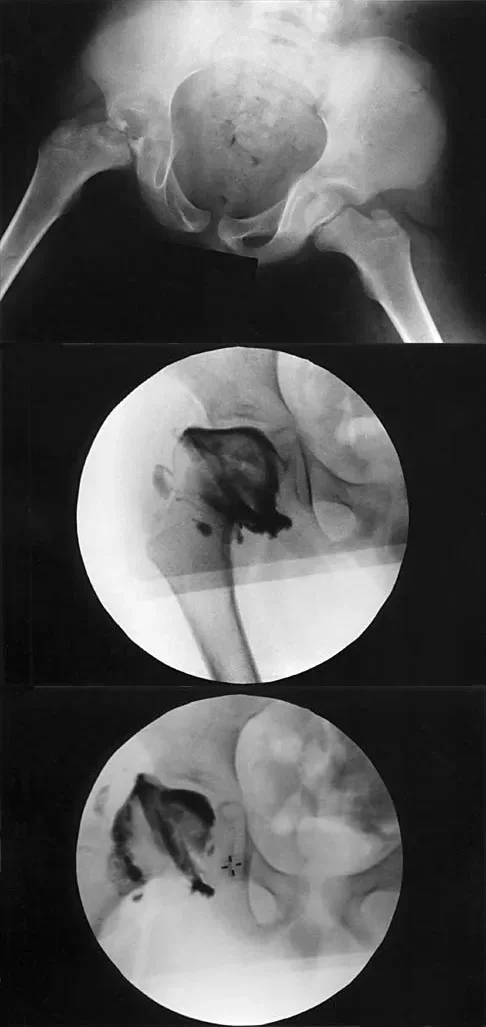

A 7-year-old boy with a history of a painless limp is diagnosed with Legg-Calvé-Perthes disease. An arthrogram is performed to evaluate joint congruency. The maximum abduction/internal rotation view is shown in Figure A, and the abduction view is shown in Figure B. The failure of the lateral epiphysis to slide under the acetabular edge with abduction, accompanied by medial dye pooling, is pathognomonic for which of the following conditions?

Explanation

Correct Answer: Hinge abduction

The arthrogram images demonstrate classic hinge abduction, a critical finding in severe Legg-Calvé-Perthes disease. Hinge abduction occurs when the enlarged, deformed lateral portion of the femoral head extrudes and impinges against the lateral margin of the acetabulum during abduction. Instead of gliding smoothly into the acetabulum, the femoral head hinges on the acetabular rim, causing the medial joint space to widen (distract), which is visualized as medial dye pooling on the arthrogram. Persistent hinge abduction prevents normal spherical remodeling of the femoral head and is an indication for surgical intervention to restore congruency.

A 7-year-old boy with a history of a painless limp undergoes an arthrogram of the hip, as shown in the provided images. The failure of the lateral epiphysis to slide under the acetabular edge during abduction is diagnostic of which of the following?

The arthrogram demonstrates hinge abduction, a severe complication of Legg-Calvé-Perthes disease where the deformed, extruded lateral portion of the femoral head hinges against the lateral acetabular margin during abduction, preventing concentric reduction. This persistent hinge abduction prevents femoral head remodeling by the acetabulum.

A 7-year-old boy with a history of a painless limp presents with limited abduction and spasm on internal rotation. Radiographs obtained during an arthrogram are shown. The failure of the lateral epiphysis to slide under the acetabular edge during abduction is diagnostic of which of the following?

Correct Answer: B

The radiographs demonstrate classic hinge abduction in a patient with Legg-Calve-Perthes disease. Hinge abduction occurs when the enlarged, deformed lateral portion of the femoral head impinges on the lateral acetabular margin during abduction, preventing the head from sliding concentrically into the acetabulum. The arthrogram shows medial dye pooling due to distraction of the joint. Persistent hinge abduction prevents proper femoral head remodeling and is an indication for surgical intervention.